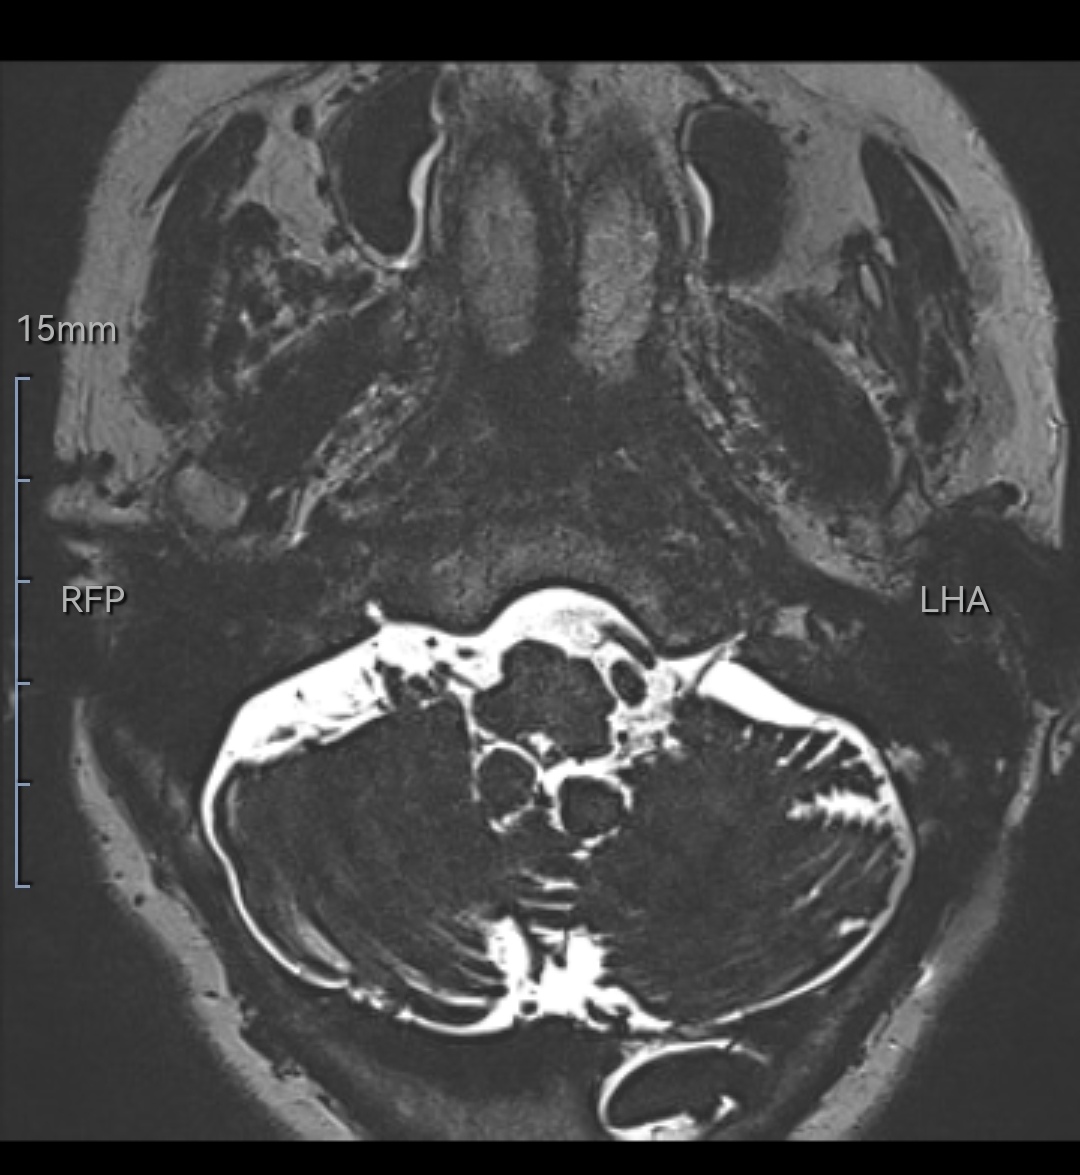

该例特点:术中见既往垫片与后组颅神经、血管粘连,硬化机化严重,剪刀、剥离子均无法撼动丝毫。

逐渐解剖,最终从后组颅神经尾端分离到操作空间,见到腹侧下方REZ区有血管卡压后组颅神经REZ区。充分松解后垫入teflon垫片,术后疼痛完全消失。